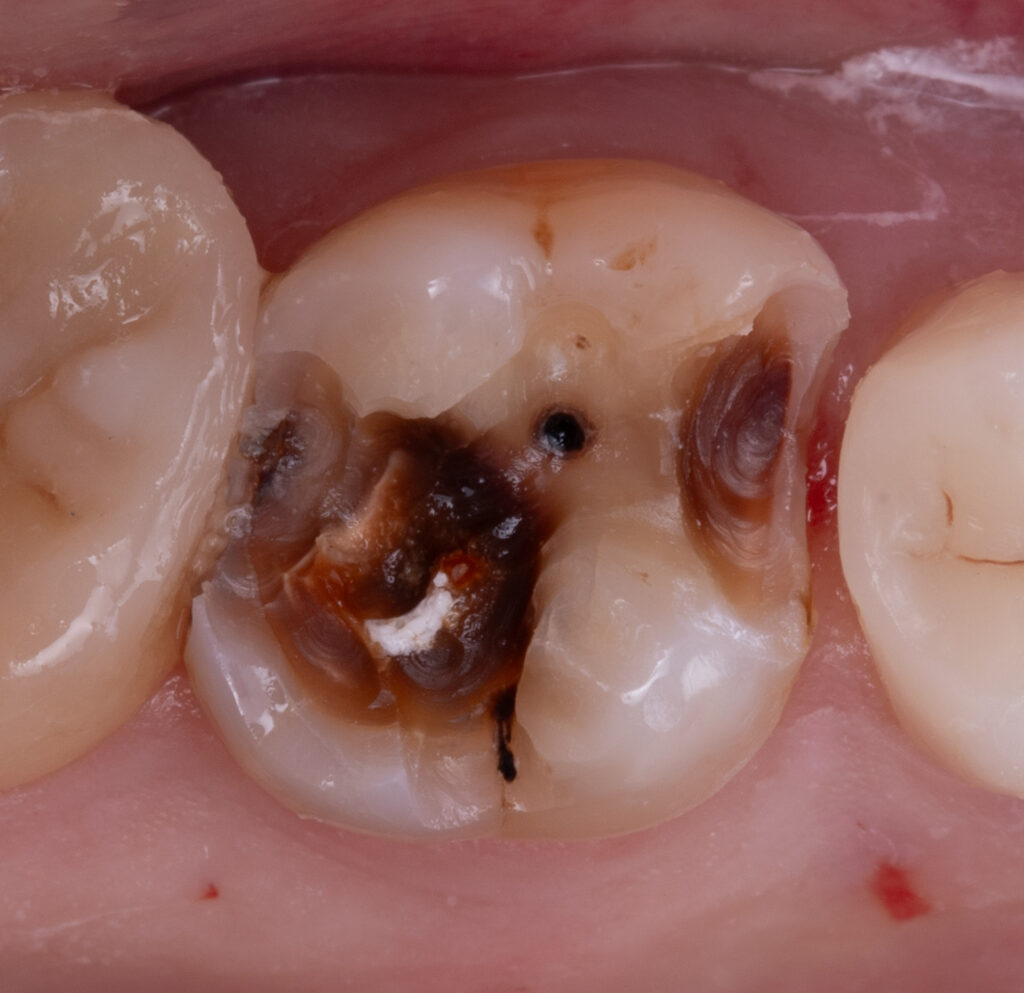

At the beginning of the treatment of deep caries on tooth 2.6, a pulp vitality (friz) test and a periapical radiograph were performed before anesthesia to confirm that the tooth was vital. Necrotomy was then carried out using a white diamond round bur and a bur on the contra-angle handpiece down to sound dentin. All infected dentin (KID) was completely removed, while cariously affected dentin (CAD) was preserved if it was hard and pigmented.